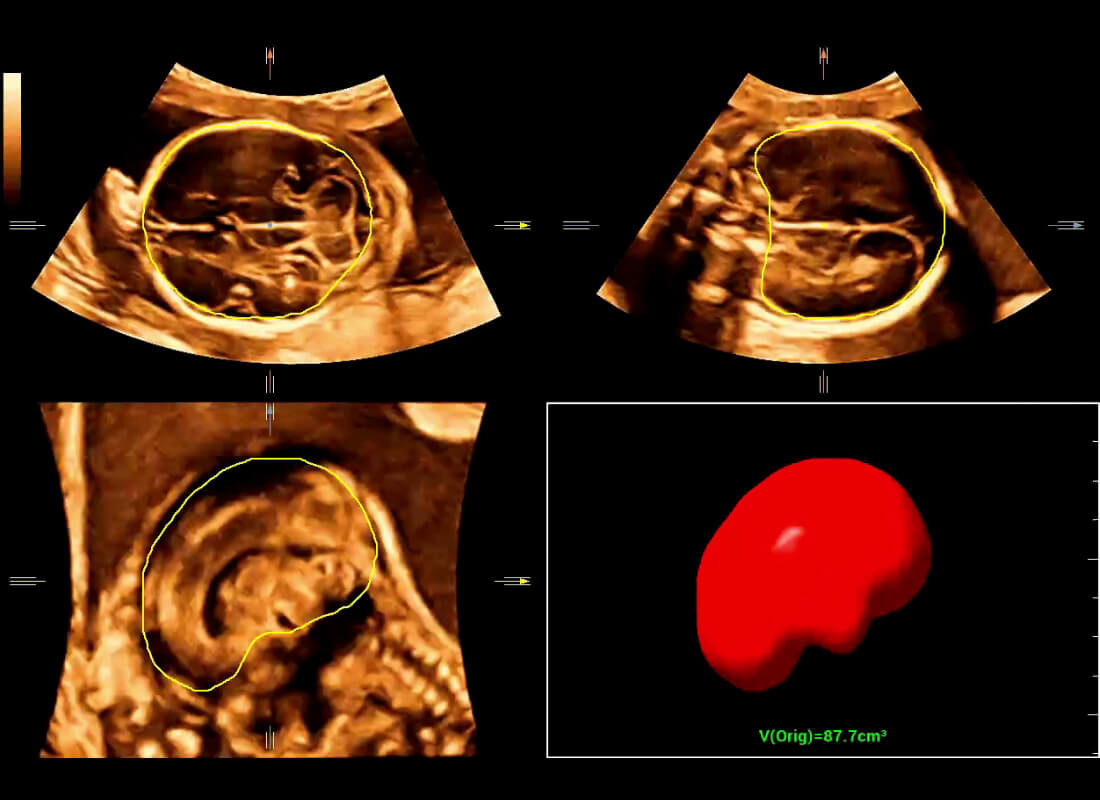

Central nervous system (CNS) malformations are one of the most common congenital abnormalities. Unfortunately, due to imaging limitations such as poor fetal position, acoustic shadowing, and operatorsŌĆÖ poor scanning skills, the MSP is particularly difficult to find in a 2D ultrasound. In this case, a faster and more user-friendly method, which automatically displays the standard planes together with the required measurements in a fetal CNS examination, could significantly boost both the quality and efficiency of clinical diagnoses.?NuewaŌĆÖs intelligent solution of fetal brain can realize automatic acquisition of brain volume data based on intelligent recognition of CNS application scenarios, intelligent generation of four fetal brain standard planes including MSP, automatic measurement of CNS biological items and automatic evaluation of fetal brain volume. More importantly, Nuewa's leading color Doppler technology can provide a clear and sensitive dynamic display of blood flow in the tiny vessels.